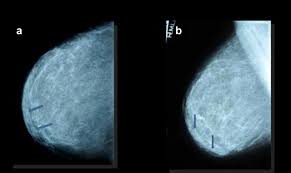

Mondor S Disease Classical Imaging Findings In The Breast Bmj Case Reports

Mondor S Disease Classical Imaging Findings In The Breast Bmj Case Reports from casereports.bmj.com

Patients usually present with a painful breast. International journal of surgery case reports. Mondor's disease is spontaneous superficial thrombophlebitis of a breast vein. Disease course and hla associations. The overlying skin does not have inflammatory. Any cancer/incurable disease mondor's disease is curable by acupressure techniques, diet, exercise, yoga. Pouchot j, sampalis js, beaudet f, et al. Mondor disease is a rare condition that is characterized by scarring and inflammation of the veins located just beneath the skin of the chest.